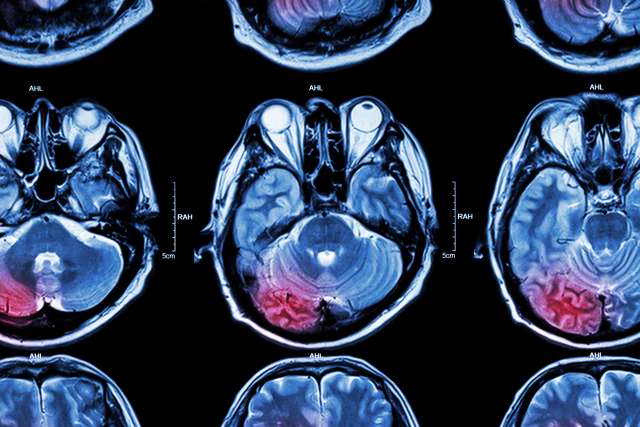

The UCLA Neuro-oncology Program is a leading comprehensive brain tumor program using molecular diagnostics, gene expression analysis, cutting edge clinical trials and advanced medical informatics to customize treatment plans for cancer patients. Our mission is to provide effective personalized medicine for brain cancer patients.

The patient evaluation and treatment approach takes advantage of our multidisciplinary collaboration with Neurosurgery, Neuroradiology, Neuropathology, and Radiation Oncology in the UCLA Brain Tumor Center to offer patients the most advanced imaging modalities, innovative and individualized chemotherapeutic protocols, and cutting edge molecularly-guided clinical trial treatments.